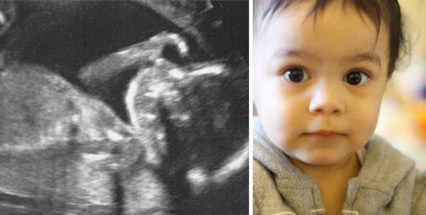

Il n'est guère surprenant que les questions liées à la conscience soient au cœur de nombre des débats éthiques les plus fondamentaux, dont ceux de l'avortement et du droit à la vie. Je profite de cette discussion pour laisser libre cours à ma fierté de jeune papa – et glisser quelques photographies de ma fille, Lalana, au cœur de l'article (ci-dessous). L'échographie a été réalisée à mi-grossesse (vingt semaines). Peu après, ses coups de pied se sont fait sentir.

La seconde image est une photographie récente. Lalana est une petite fille de deux ans; elle n'arrête pas de courir en tous sens, et dispose d'un vocabulaire de quelques centaines de mots. Elle peut nous parler d'évènements survenus il y a quelques jours, voire quelques semaines – et ce parce que ces souvenirs lui procurent souvent un sentiment d'excitation intense. Elle peut également conserver en mémoire des vœux qu'elle souhaite voire se réaliser. Prenons un exemple: nous lui disons, au détour d'une conversation, qu'elle pourra faire des bulles lorsque nous seront rentrés à la maison. A peine la porte d'entrée franchie, plusieurs heures plus tard, la voilà qui s'élance vers l'étagère abritant le tube à bulles et qui s'écrie: «Bubulles! Bubulles!». Elle a des avis très arrêtés; sait ce qu'elle aime et ce qu'elle déteste - et sa personnalité (sensibilité émotionnelle, effronterie, et une opiniâtreté inquiétante) est déjà bien marquée.

Je me pique d'objectivité depuis le début de ma vie d'adulte. J'ai toutefois découvert –- avec un certain embarras – que ma fille était la principale exception à cette règle. La force de mon amour pour elle me déconcerte - tout comme la fierté qu'elle m'inspire, et la facilité avec laquelle je déforme la réalité pour la rendre exceptionnelle en tous points. Mais lorsqu'il m'est possible de prendre du recul, une question m'apparait: à quel stade ma fille est-elle devenue consciente? Elle l'est aujourd'hui, bien évidemment, puisqu'elle peut me confier ses pensées par oral. Mais quand a-t-elle commencé à ressentir le monde qui l'entoure? Sur le plan personnel et instinctif, j'estimais que ses premiers éclats de rire face à mes pitreries (lorsqu'elle était âgée de quelques mois) étaient la preuve de l'existence d'une conscience significative. Mais était-elle consciente bien avant cette période? L'était-elle dans le ventre de sa mère, lorsqu'elle donnait coup de pied sur coup de pied? L'apparition de sa conscience ne date-t-elle que du jour de sa naissance, lorsqu'elle a ouvert les yeux sur le monde extérieur pour la première fois?